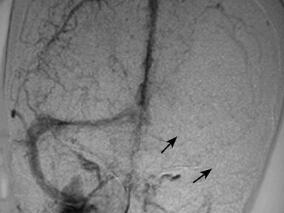

1小时条评论硬脊膜动静脉瘘(SDAVF)是脊髓血管畸形最常见的一种类型,多缓慢起病,但本例患者突发双下肢无力伴小便失禁,如何防止误诊? 硬脊膜动静脉瘘(spinal dural arteriovenous fistula,SDAVF)是脊髓血管畸形最常见的一种类型,约占70%[1]。本文报道一例表现为突然...